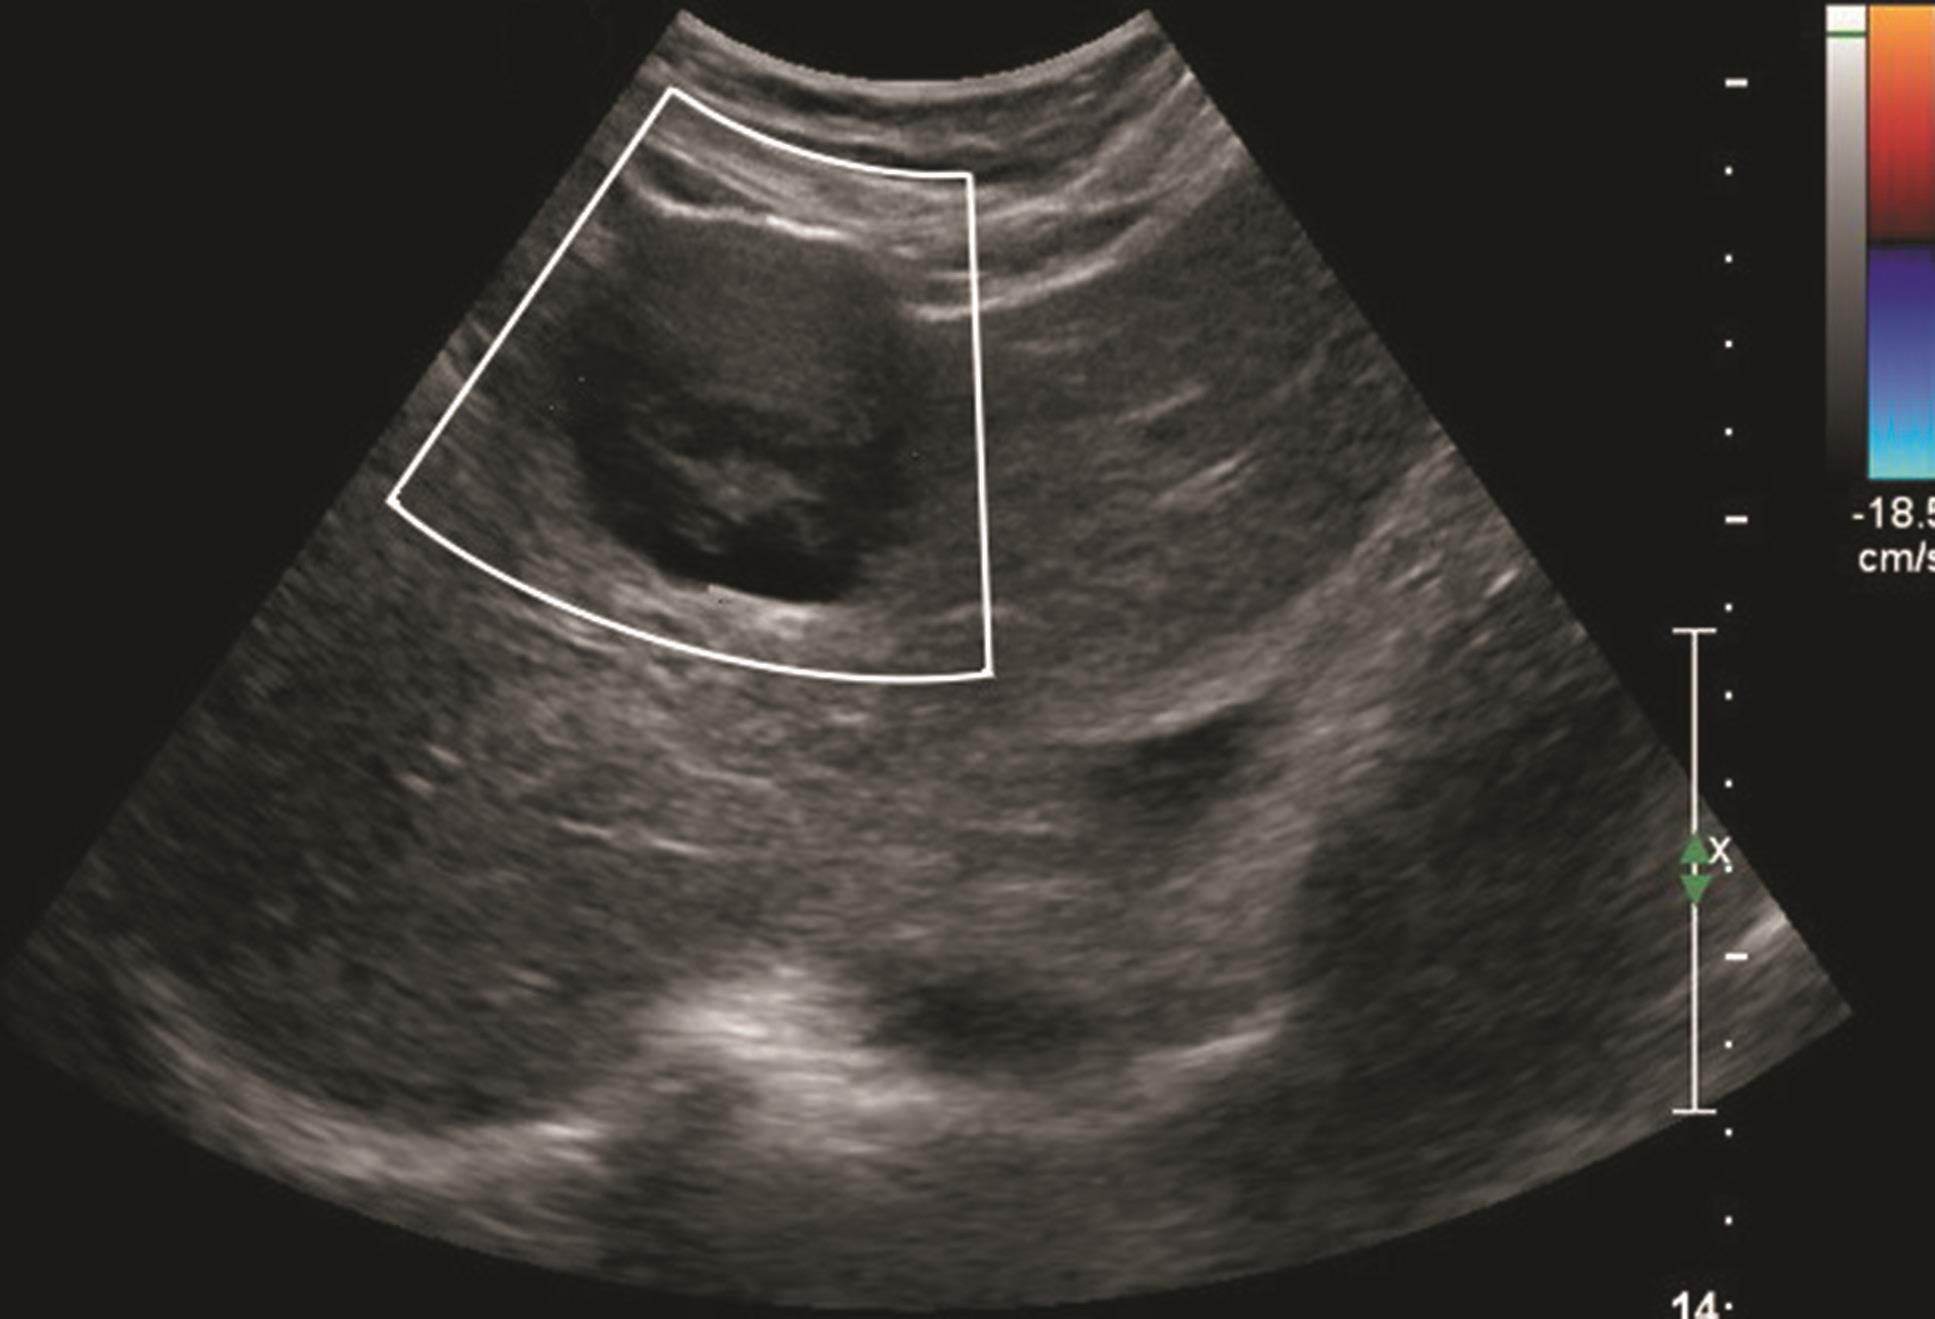

(4)彩色血流特征:

胆管细胞癌大部分为乏血供,CDFI可显示肿块内零星分布的点状血流信号(图1-7-5)。

图1-7-5 肝内胆管细胞癌CDFI图像

CDFI显示病灶周边可见点状血流信号